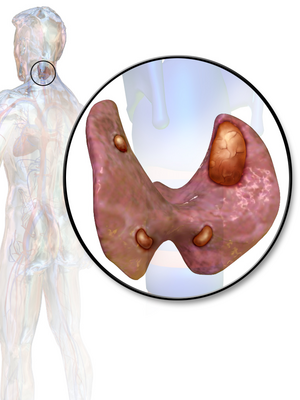

غدوم الجار درقية هو ورم حميد في الغدة الجار درقية. عادة ما يسبب فرط نشاط جارات الدرقية. هناك عدد قليل جدًا من التقارير عن غدومات الجار درقية التي لم تكن مرتبطة بفرط نشاط جارات الدرقية.[1]

عادة ما يكون لدى الإنسان أربع غدد جارات درقية تقع على السطح الخلفي للغدة الدرقية في الرقبة. من أجل الحفاظ على استقلاب الكالسيوم ، تفرز الغدد جارات الدرقية هرمون الغدة الجار درقية (PTH) الذي يحفز العظام على إطلاق الكالسيوم والكلى لإعادة امتصاصه من البول إلى الدم ، وبالتالي زيادة مستوى الكالسيوم في المصل. يتعارض عمل الكالسيتونين مع هرمون الجار درقية. عندما يتسبب غدوم الجار درقية في فرط نشاط جارات الدرقية ، يتم إفراز المزيد من هرمون الغدة الجار درقية ، مما يؤدي إلى ارتفاع تركيز الكالسيوم في الدم ، مما يؤدي إلى فرط كالسيوم الدم.[2]